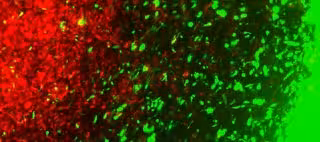

CSTI/KHALID SHAH LAB

Para probar ambos enfoques, el equipo utilizó modelos de ratón de cáncer de cerebro primario y recurrente y cáncer de mama que se diseminó al cerebro. El equipo observó la migración directa de células modificadas genéticamente a los sitios de los tumores y encontró evidencia de que las células modificadas específicamente dirigieron y mataron el cáncer recurrente y metastásico en los ratones.